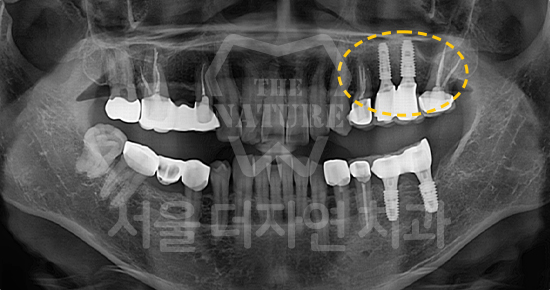

#Maxillary Bone Grafting

-

BEFORE: 2021.11.02

AFTER: 2022.01.19